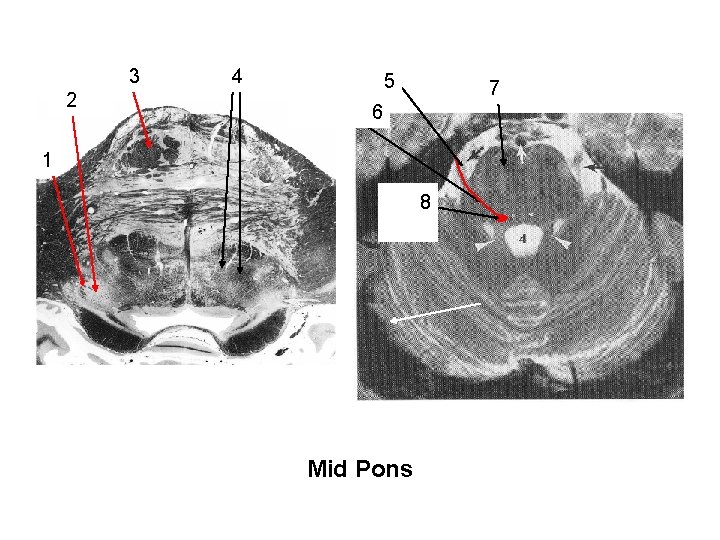

reticular formation with descending rubrospinal descending cortical fibers trigeminal nerve motor nuc. & nerve roots of V 3 2 4 5 descending cortical fibers 7 6 Nerve Roots of V 1 motor nucleus of V 8 Mid Pons